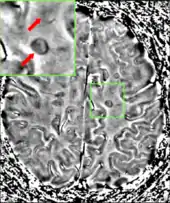

Central vein signs (CVSs) have been proposed as a good indicator of MS in comparison with other conditions causing white lesions.[71][72][73][74] One small study found fewer CVSs in older and hypertensive people.[75] Further research on CVS as a biomarker for MS is ongoing.[76]